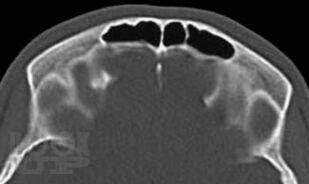

Рентгенографическая и компьютерно-томографическая диагностика острых и хронических синуситов

Монография посвящена применению классической рентгенографии и рентгеновской компьютерной томографии для диагностики острых и хронических воспалительных заболеваний околоносовых пазух. Результаты обоих исследований сопоставлены между собой по разработанной авторами методике, предложены адаптированные к практической работе подходы к обоснованному выбору указанных методов рентгенодиагностики синуситов. Книга хорошо иллюстрирована, содержит примеры описания рентгенограмм и компьютерных томограмм околоносовых пазух.